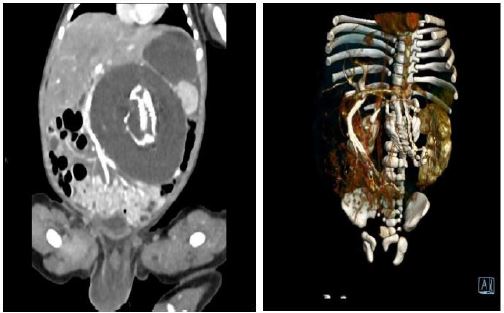

A 28-year-old pregnant woman, gravida 2 para 1 abortion 1, presented to our department with an abnormal ultrasound scan at 22 weeks’ gestation that revealed a fetal abdominal mass. Initially this was thought to be a teratoma. Family history was negative for congenital malformations, and there was no history of medication and drug use during pregnancy. Upon detailed sonography scanning in our institution a 25 mm in diameter heterogeneous abdominal mass with an internal density mass was visualized. The mass was well circumscribed and power doppler investigation revealed normal blood flow. Monthly repeat studies showed the mass steadily enlarging. A formal follow-up ultrasound at 26 weeks gestation demonstrated that the mass was 38 mm in diameter with rudimentary spine, ribs, ilium and a limb. A subsequent magnetic resonance imaging verified the heterogenous mass with multiple bones and vertebral body. At this stage an endoparasitic FIF was diagnosed. Amniocentesis that performed at 23 weeks’ gestation demonstrated a normal karyotype and testing of maternal alpha-fetoprotein levels was not performed. The boy was born full term by normal vaginal delivery with a birth weight of 3080 g. He had Apgar scores of 10 and 10 at 1 and 5 min, respectively. At laparotomy shortly after birth an encapsulated retroperitoneal mass was resected. Gross anatomy and pathological examination demonstrated a fetus in fetu, as well as DNA fingerprinting techniques confirming identical genetic material shared by the child and the mass. From the gross anatomy the lower part of body with a limb and an umbilical cord could be seen. The baby did well postoperatively.

Figure 3: MRI images of newborn after birth. A vertebral axis can be seen in the cavum abdominis of the infant.